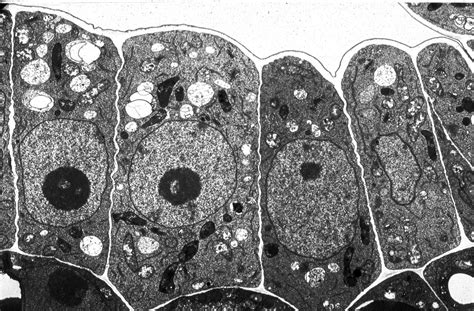

Electron Microscopes

Electron microscopes use a beam of electrons instead of light to produce high-resolution images. They can magnify up to 2 million times, revealing detailed structures within cells, such as organelles and molecular components. There are two main types of electron microscopes:

• Transmission Electron Microscope (TEM): Provides detailed internal structures by passing electrons through thin sections of the sample.

When observing under microscope cells, several key structures can be identified:

Nucleus

The nucleus is the control center of the cell, containing the genetic material (DNA) and regulating cell activities. It is surrounded by a nuclear membrane and contains nucleoli, which are involved in ribosome production.

Cytoplasm

The cytoplasm is the gel-like substance that fills the cell, containing various organelles and providing a medium for biochemical reactions. It is enclosed by the cell membrane, which regulates the movement of substances in and out of the cell.

Organelles

Organelles are specialized structures within the cell that perform specific functions. Some key organelles include:

• Mitochondria: Known as the powerhouses of the cell, they generate energy through cellular respiration.

• Endoplasmic Reticulum (ER): Involved in protein synthesis and lipid metabolism. It comes in two forms: rough ER (with ribosomes) and smooth ER (without ribosomes).

• Golgi Apparatus: Modifies, sorts, and packages proteins and lipids for transport within the cell or secretion.

• Lysosomes: Contain digestive enzymes that break down waste materials and cellular debris.

• Ribosomes: Sites of protein synthesis, found either freely in the cytoplasm or attached to the rough ER.